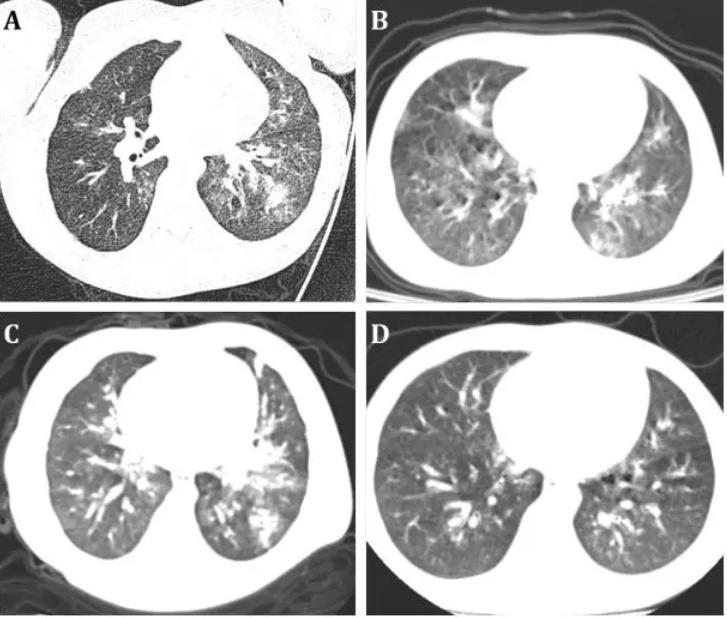

新型冠状病毒是一种RNA病毒,具有高度的变异性,这意味着病毒在传播过程中可能发生变异,产生新的亚型,这些亚型在传播能力、致病力等方面可能存在差异,新型冠状病毒主要通过飞沫传播和接触传播,这也使得病毒的传播速度非常快,病毒主要攻击人类的呼吸系统,导致发热、咳嗽、呼吸困难等症状,严重的情况下,可能导致肺炎甚至死亡。